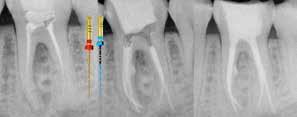

Questa fase è preceduta dalla misurazione della lunghezza del canale, attraverso l’utilizzo di un localizzatore di apice collegato ad un lima manuale in acciaio avente un diametro idoneo a restare in contatto con le pareti del canale in modo da evitare false misurazioni.

Il glide path (cateterismo) consiste nel creare un sentiero di scorrimento in direzione corono-apicale. In letteratura, si afferma che un adeguato sentiero di scorrimento si raggiunge quando un file K 15 è in grado di percorrere senza interruzioni l’intero canale, dall’imbocco sino al forame apicale. In questo modo si facilita il lavoro dei successivi strumenti di sagomatura che potranno percorrere in modo passivo l’intero canale.

5. Stabilire la lunghezza di lavoro con una radiografia pre-operatoria

∙ Si consiglia una valutazione radiografica preoperatoria per determinare l’anatomia canalare.